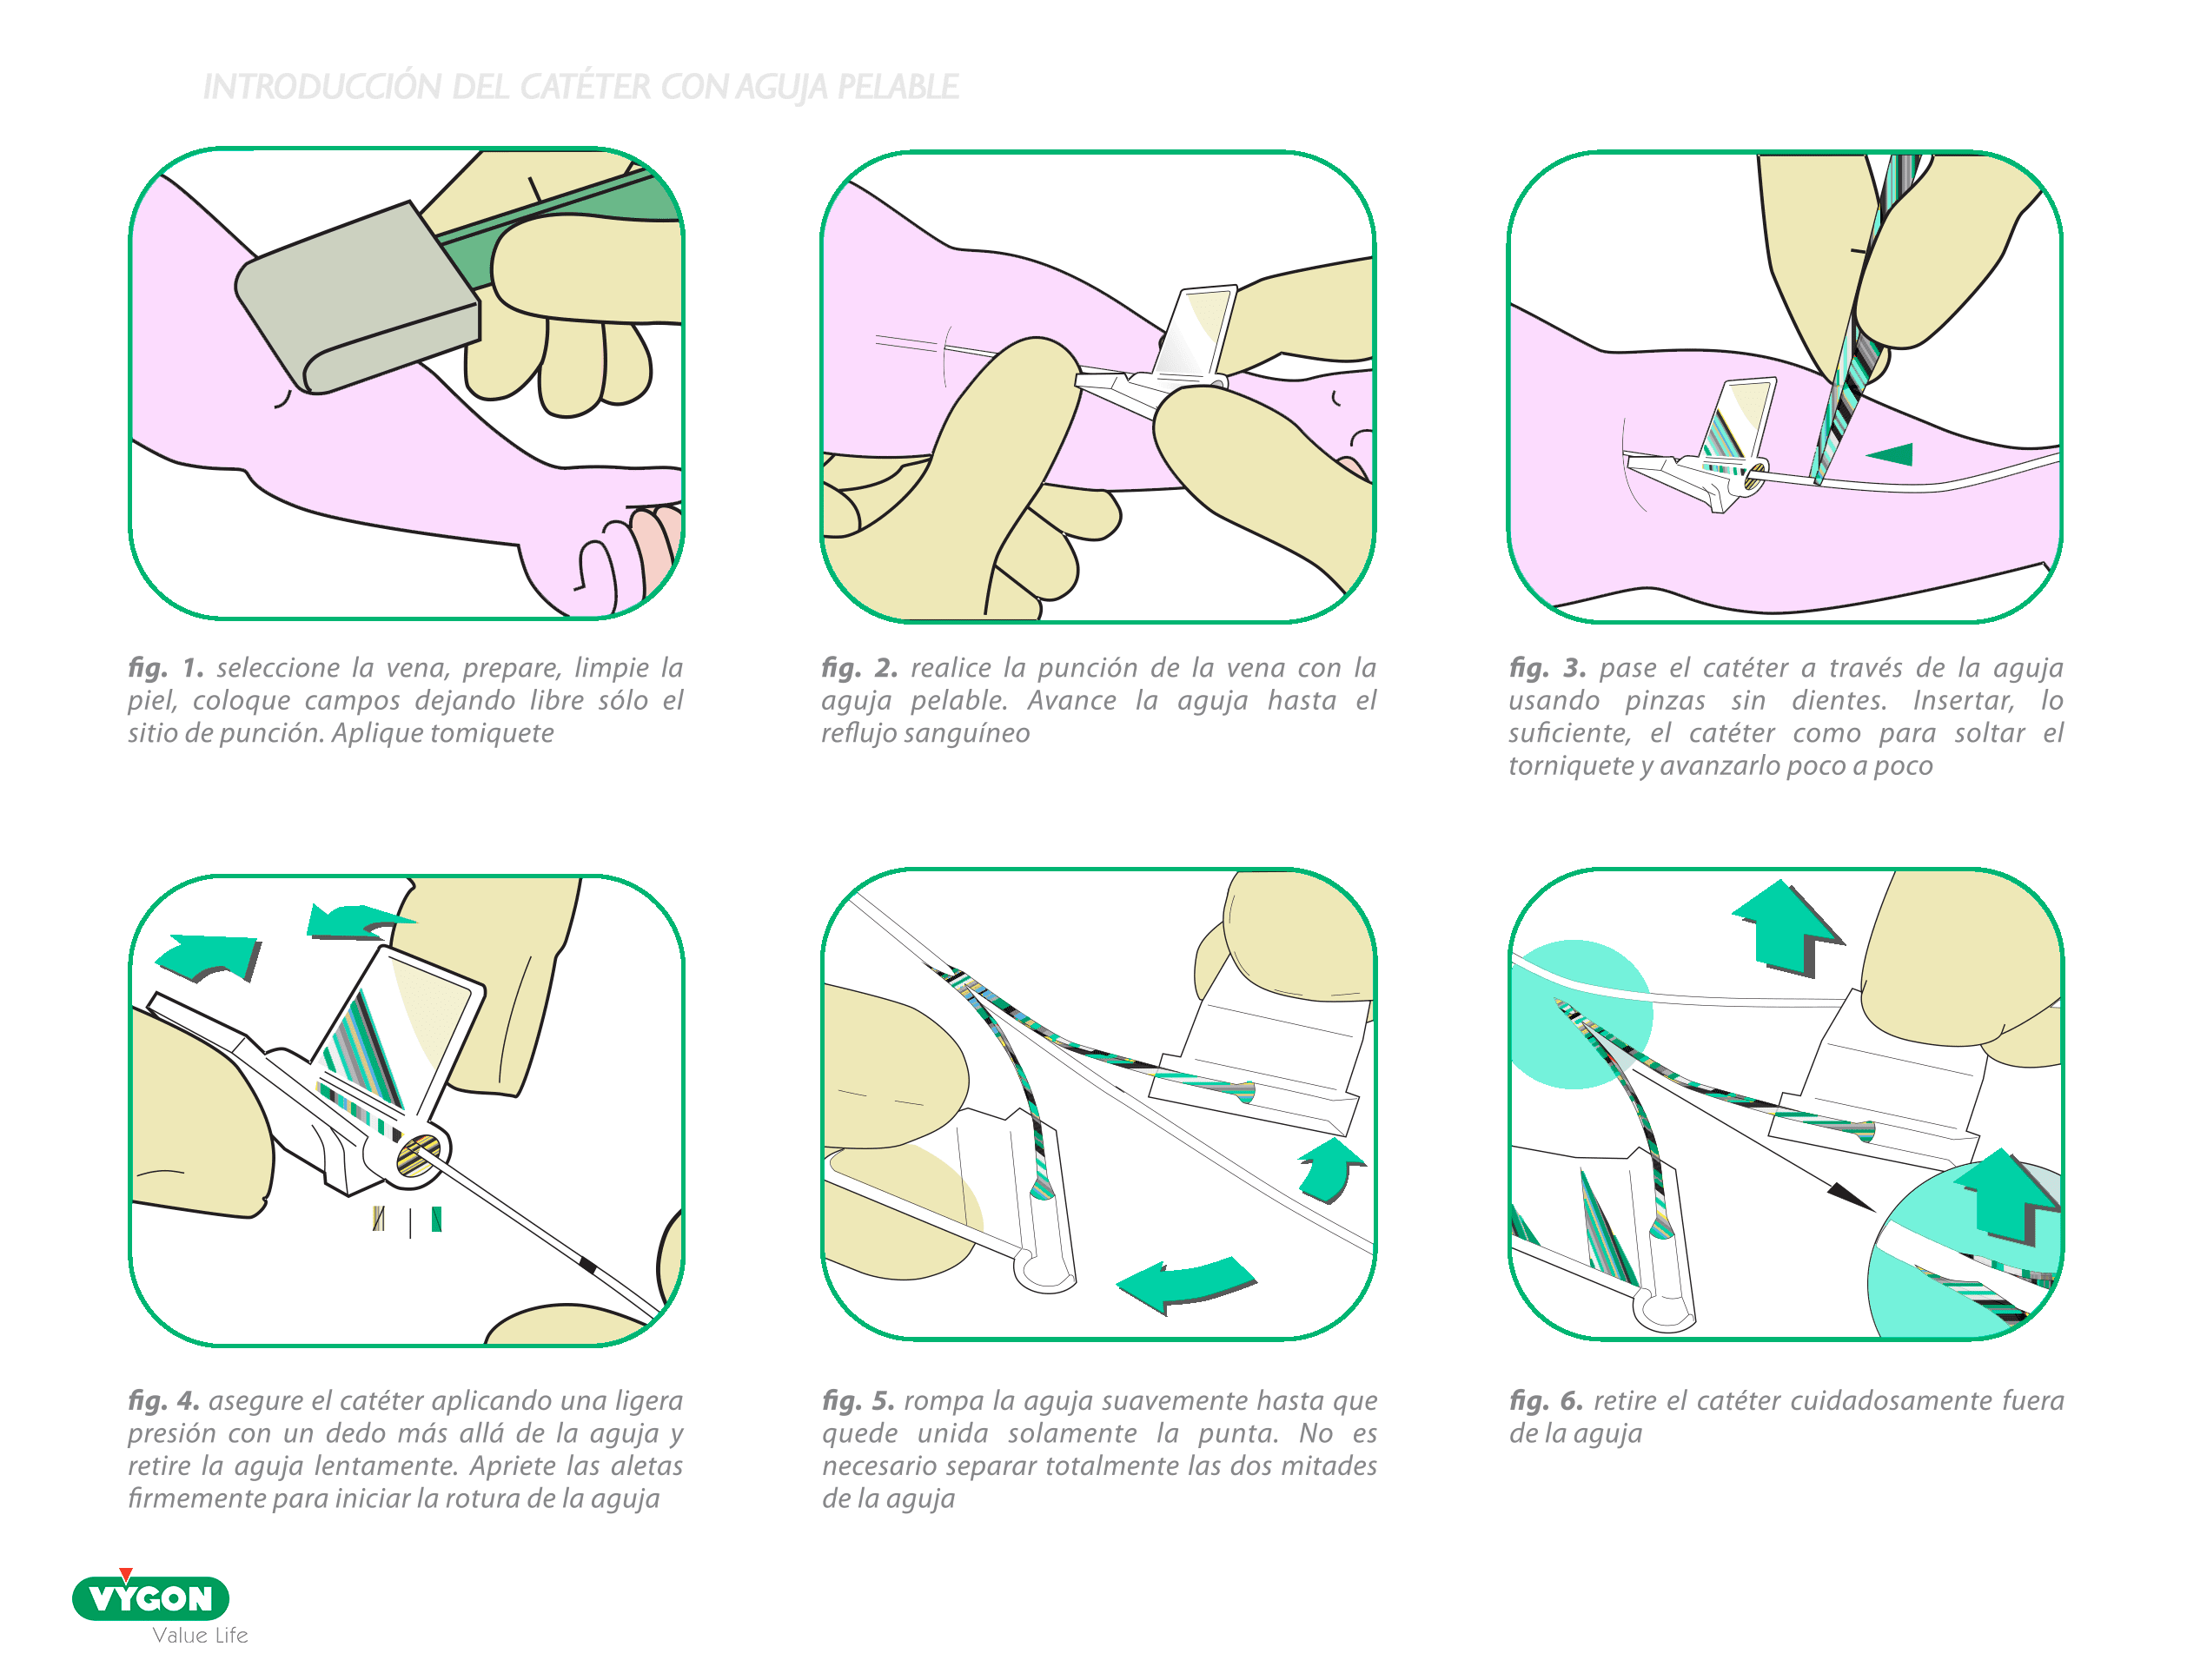

AGUJA PELABLE

Al ser un dispositivo rompible con pabellón y aletas rígidas transparentes, este introductor se puede usar con cualquier PICC neonatal, de 1Fr o 2Fr.

VENTAJAS

- Introductor fino (20G y 24G) y corto (18 y 25mm) que permite la canalización de catéteres en venas de calibre muy reducido

- Uso con PICC de una sola pieza: menos riesgo de infección (ver anteriormente)

- Facilita la inserción del catéter en el introductor al tener un pabellón con abertura ancha (cono)

INCONVENIENTES

- Curva de aprendizaje, especialmente si se parte de la técnica con aguja mariposa: conocer la presión a aplicar para romperla

- Resulta imprescindible ser metódico para no separar completamente con el fin de evitar tener 2 extremidades cortopunzantes a la hora de desecharla

- Es necesario esperar el retorno de sangre en el pabellón para que ver que está en vena